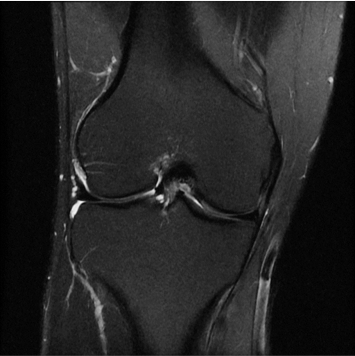

1:28 minConventional

384 x 256 (4 NEX)

3:00 minIAI (Innovative AI)

384 x 256 (2 NEX)

1:29 minReduced Scan Time

384 x 256 (2 NEX)

1:29 minConventional

IAI는 AI Deep learning을 통해 기존 장비의 촬영 프로토콜을 최적화합니다.

기존 프로토콜 대비 촬영 시간을 50% 단축시키며, 이미지 퀄리티는 증가합니다.